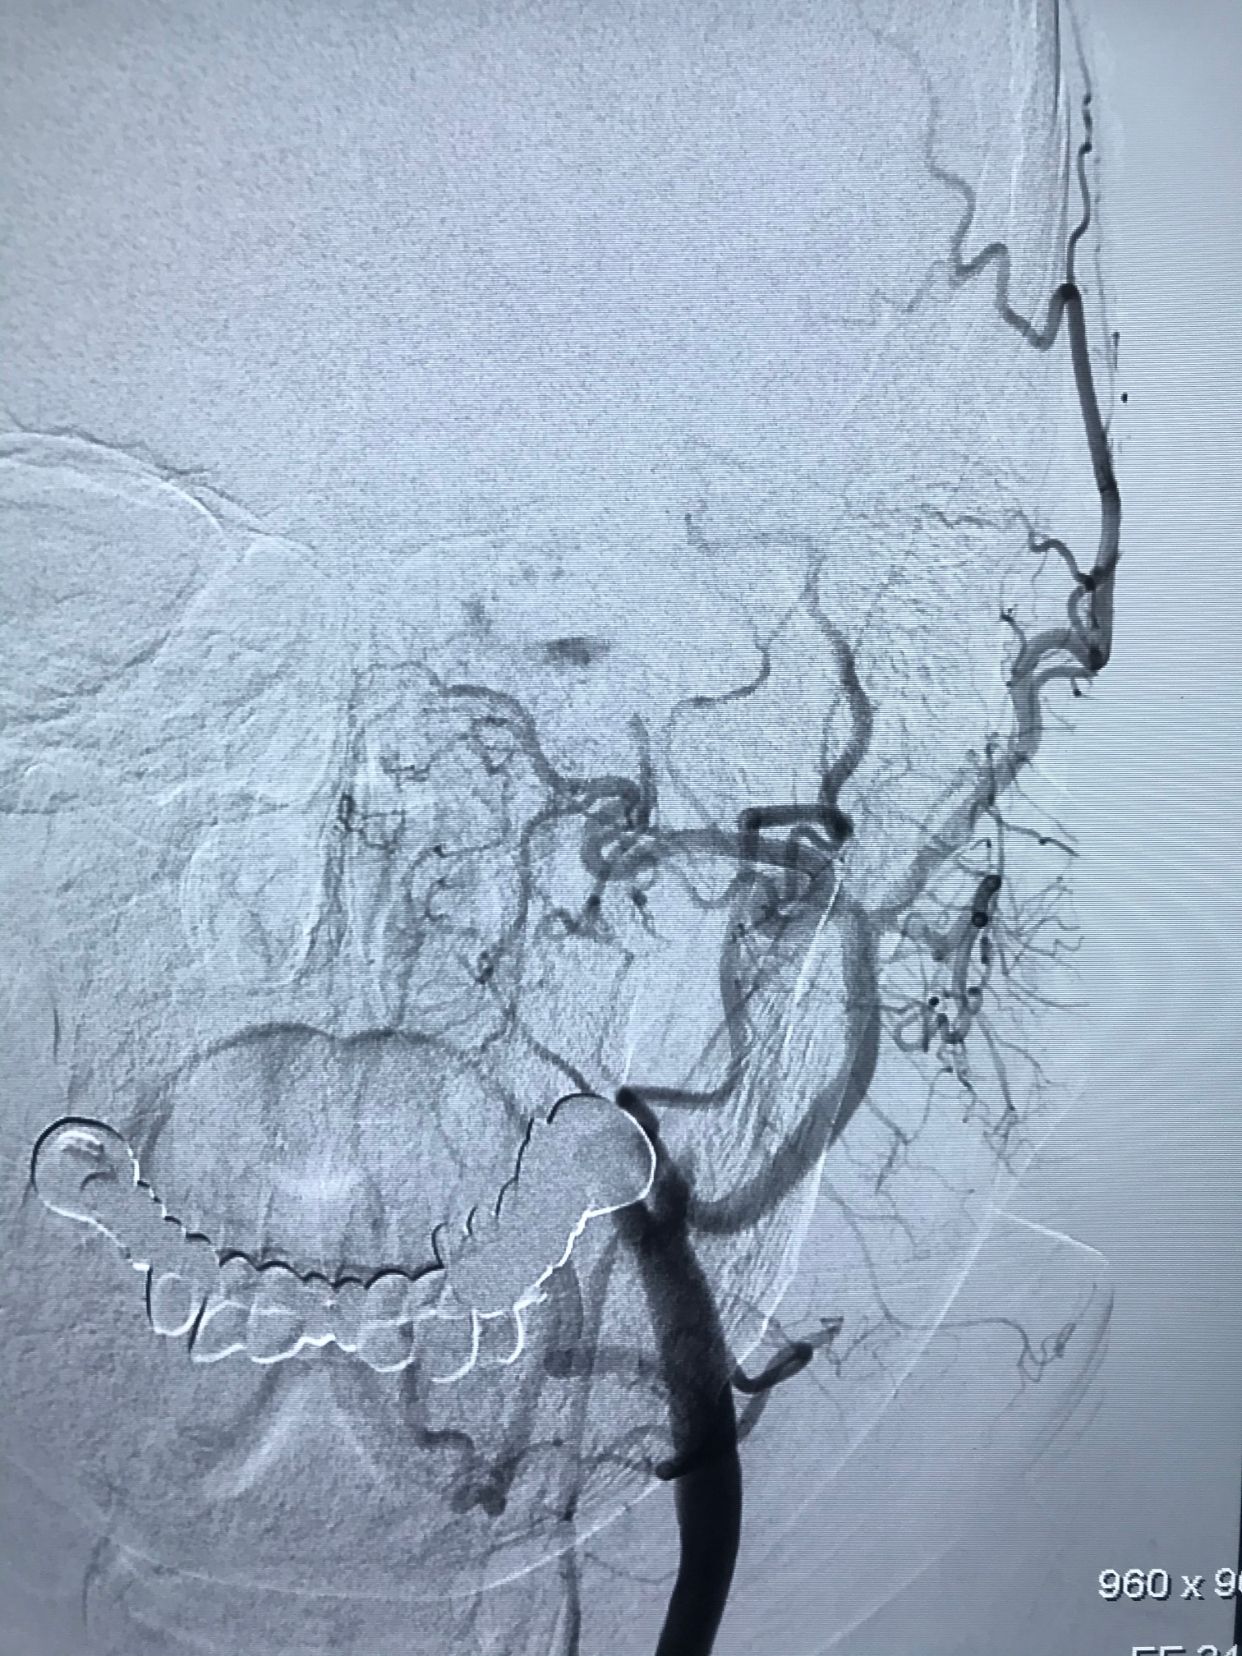

术后正位造影,颅内血管显影良好!

术后侧位造影!